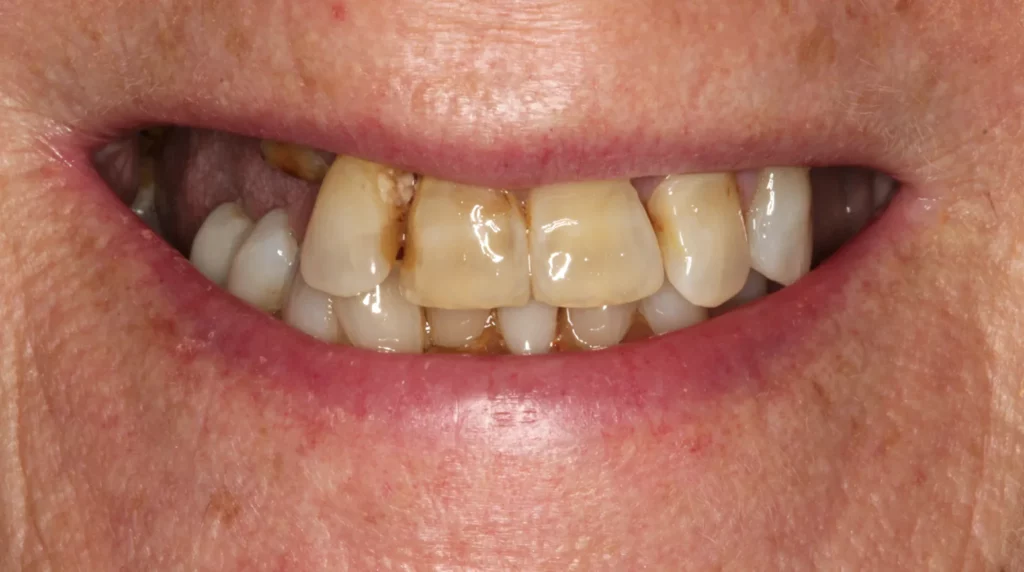

One New Year’s Eve, we received a phone call from a distressed lady who said her top front bridge had fallen out unexpectedly. Regrettably, the two teeth that supported the bridge had decayed and couldn’t be fixed. The patient wanted to avoid wearing a long-term denture and had always longed for a better smile. She was very self-conscious when smiling, and like many people, having her photo taken was not her favourite event.

The above shows the two rotten teeth that were removed and went on to be replaced by two implants with gold posts.

Below is a temporary bridge worn during the treatment phase.

To achieve smile symmetry, the gum was recontoured around the adjacent teeth while others had gum grafts placed to reduce the speed of gum recession. Both the health and appearance of the smile were addressed.